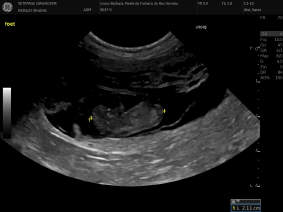

Am 4. Mai 2022 Abends ab 21.30 Uhr hat uns unsere süsse Neele 4 Rüden und 2 Hündinnen geschenkt. Wir freuen uns über diese neuen Erdenbürger und sind gespannt über den weiteren Verlauf der Welpen.